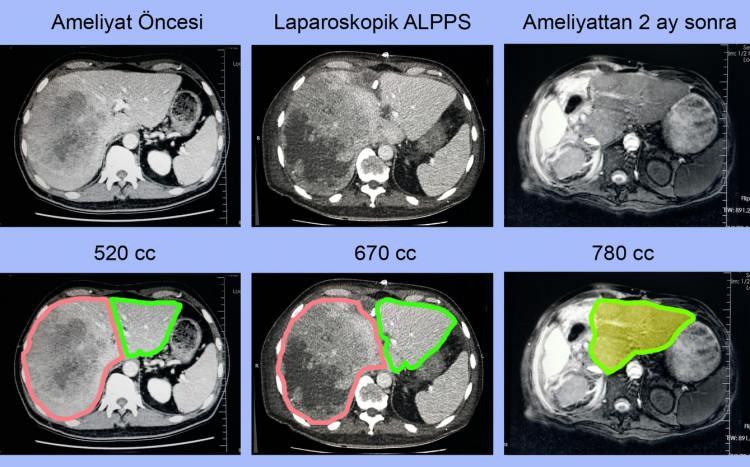

Karaciğer, karaciğer içi ve safra kanallarının kötü huylu tümörü: